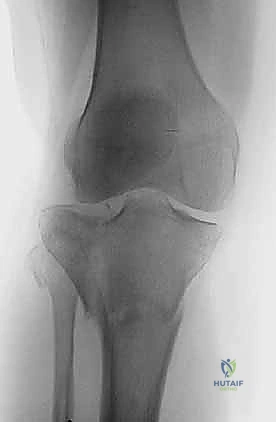

2. التصوير الإشعاعي (X-rays)

الخطوة الأولى هي التقاط صور أشعة سينية من عدة زوايا (أمامية خلفية، وجانبية). تعطي الأشعة السينية فكرة عامة عن وجود الكسر وموقعه، لكنها غير كافية لتقييم الكسور ثنائية اللقمة المعقدة.

3. الأشعة المقطعية المحوسبة (CT Scan) - المعيار الذهبي

لا يمكن إجراء جراحة لكسر ثنائي اللقمة دون إجراء أشعة مقطعية (يفضل مع إعادة بناء ثلاثية الأبعاد 3D).

* توفر الأشعة المقطعية خريطة دقيقة لكل شظية عظمية.

* تحدد مقدار الانخساف في السطح المفصلي بالمليمتر.

* تكشف الشظايا المخفية، خاصة في الجزء الخلفي من الركبة (Posterior Coronally oriented fragments) والتي تتطلب خطة جراحية خاصة لتثبيتها.